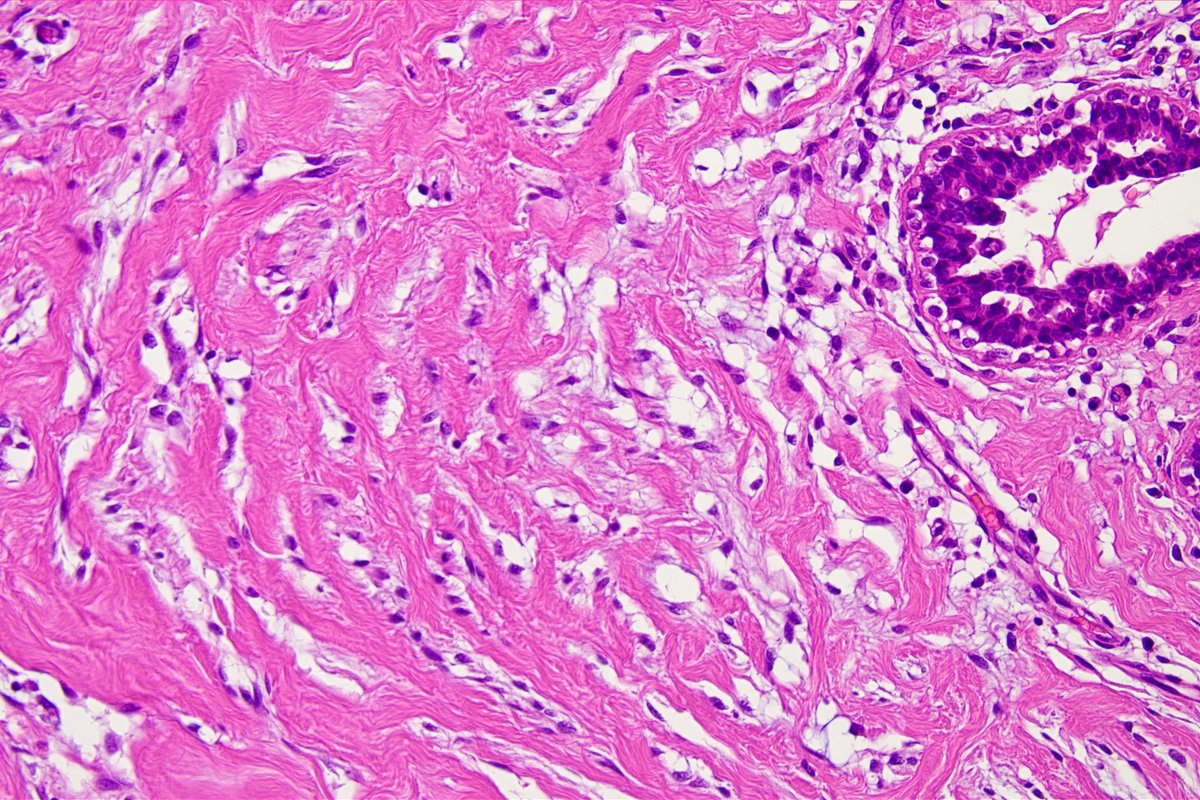

Mismatch-repair deficient endometrioid carcinoma. HE and MLH-1(+), MSH-2(-), MSH-6(-), PMS2(+). Isthmus of uterus. #Pathology #Pathologist #GynPath